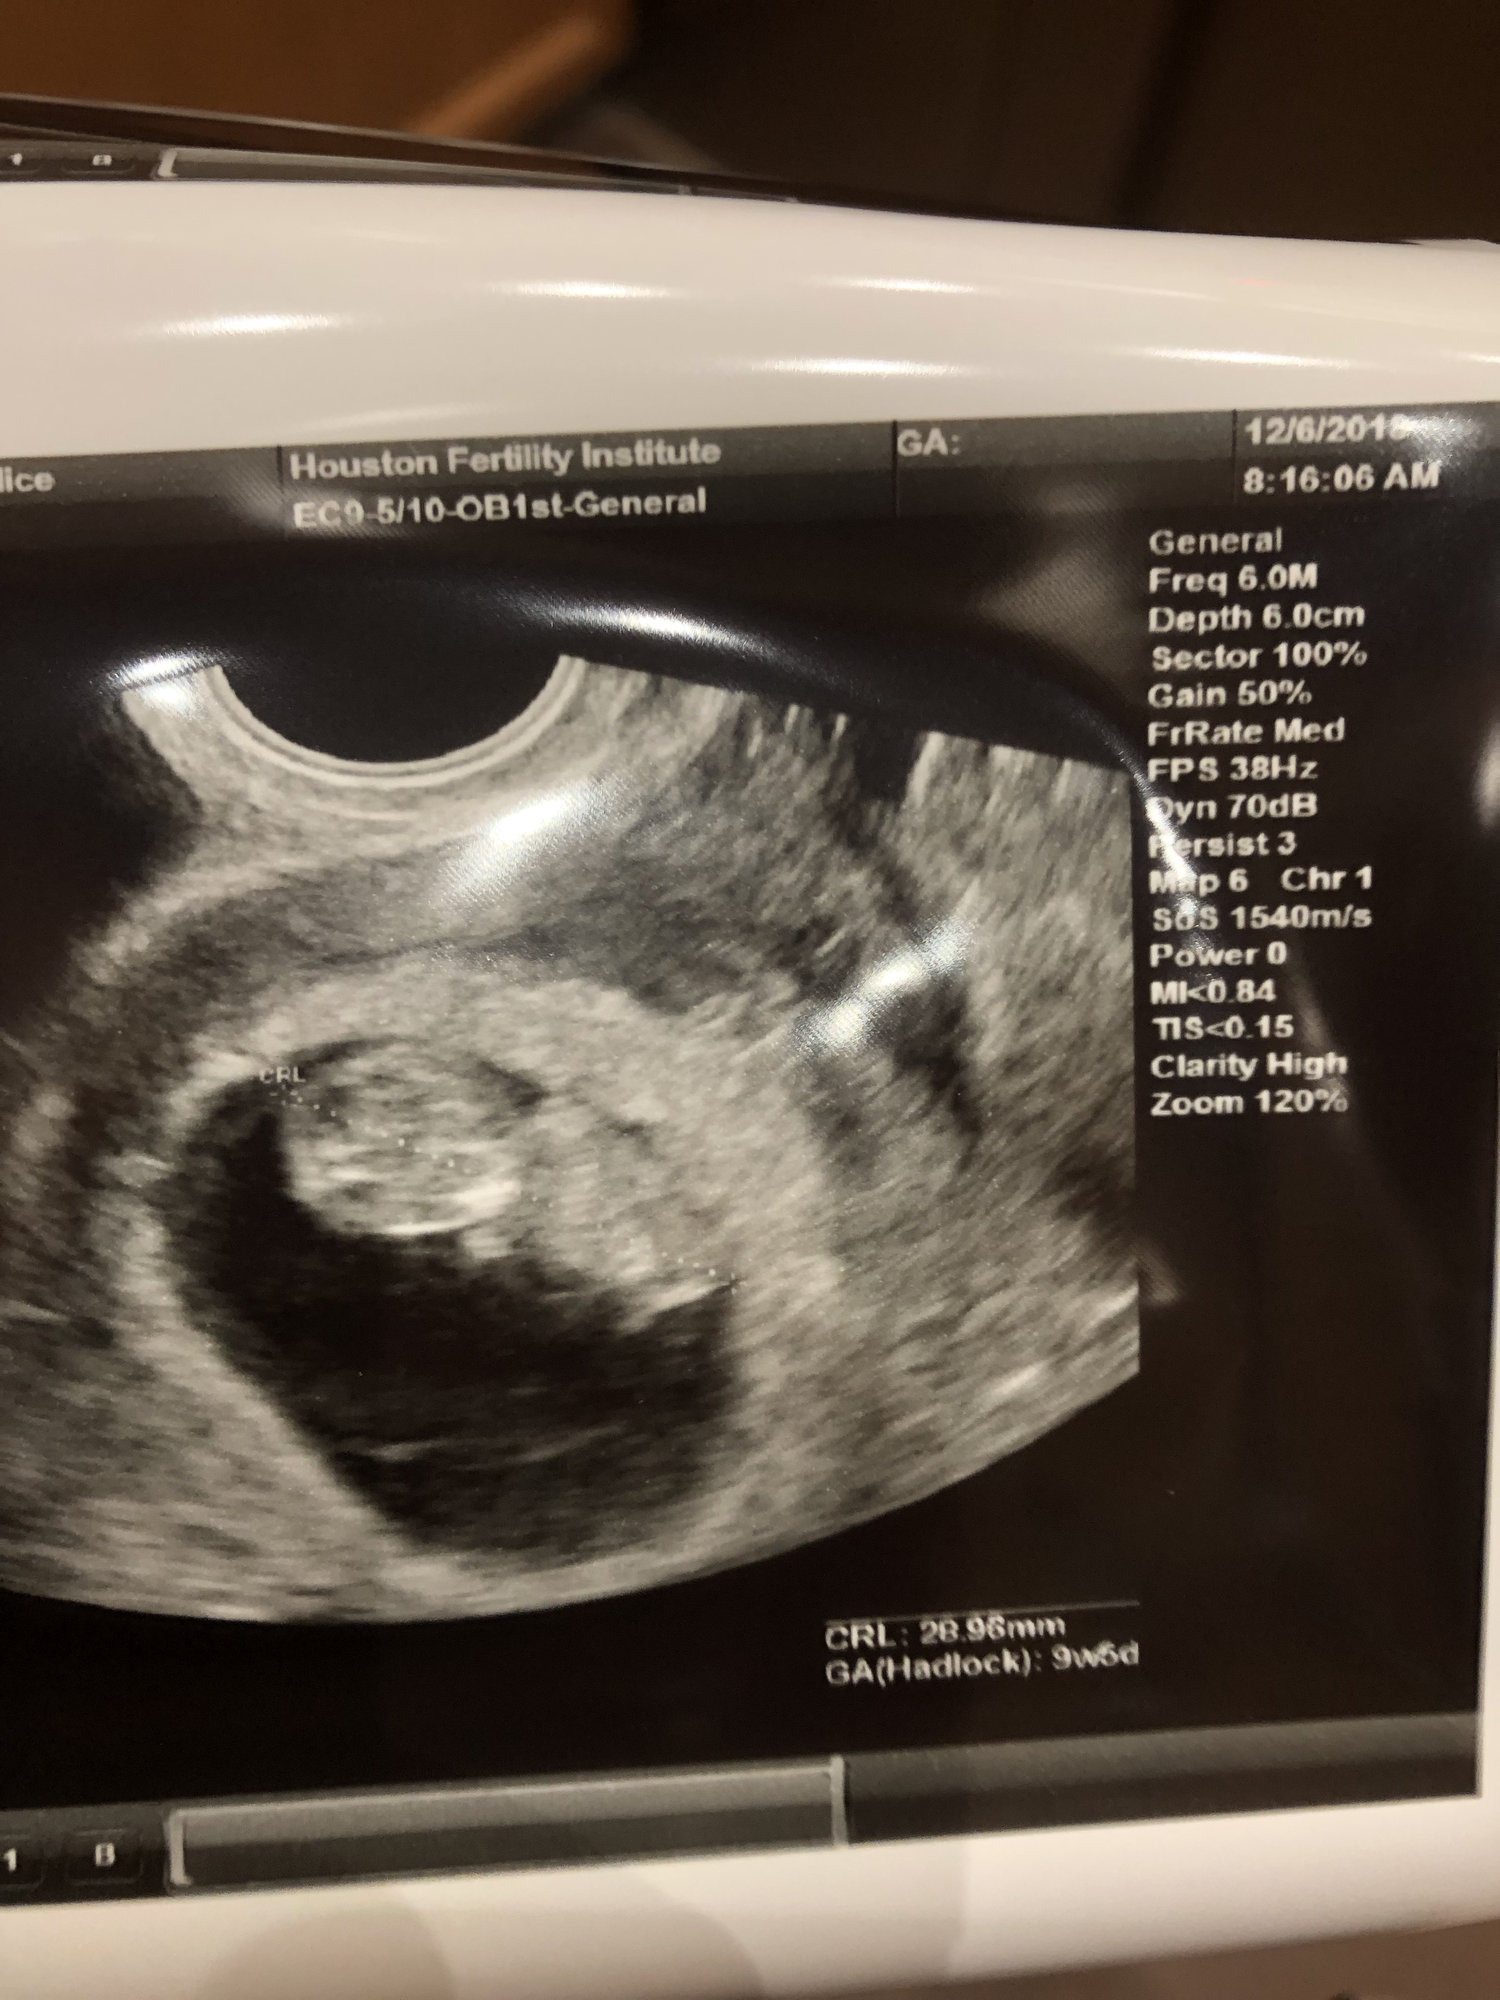

Went and saw baby again today, and learned that I am actually 10weeks1day not 9weeks4days. They are keeping my original due date since baby is growing. Next appointment will be with my OB to do the DNA testing